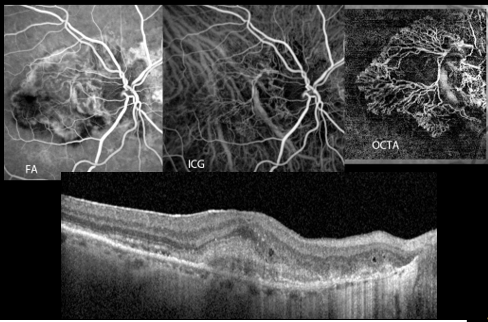

If your doctor finds leakage, or exudation, under your retina and the diagnosis of Exudative Age-Related Macular Degeneration (ARMD) is made, he/she may inject an imaging dye into your vein and take photos of the macula/retina. This test is critical to determine what type of Exudative ARMD you have - there is no 'one size fits all'. There are many phenotypes, or different ways in which the disease presents. This is important because different phenotypes respond to anti-VEGF drugs differently (more later). OCT, OCT Angiography (OCTA), flourescein angiography (IVFA), and indocyanine green (ICG) are all used to best diagnose, treat and follow these diseases.

The image above shows how neovascularization can be appreciated on each modality. Below, a cross section of the retina shows neovascularization on OCT. The photo on the top right shows how this neovascularization is appreciated on OCTA, the middle photo by ICG and the top left photo on IVFA.